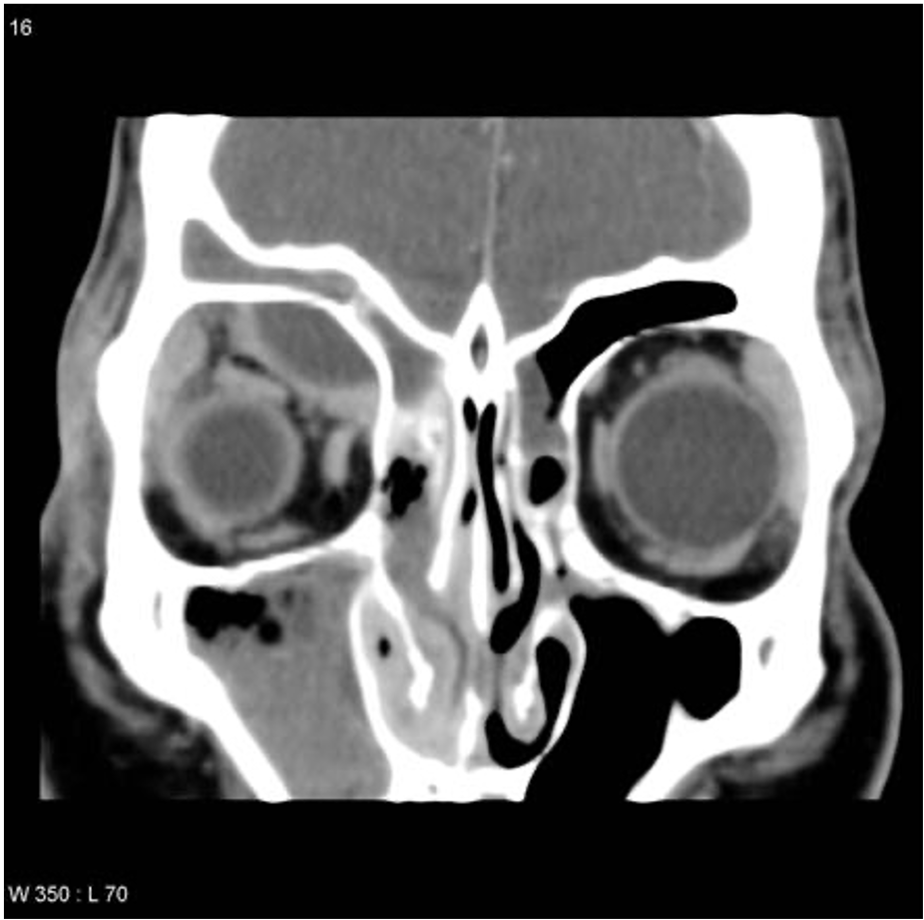

Sub Periosteal Abscess Coronal contrast-enhanced CT image of right orbit showing extraconal marginally enhancing fluid collections located superonasal, consistent with subperiosteal abscess. These are present in continuation with opacified right ethmoidal air cells and right maxillary antrum with soft tissue density with hyperdense content.